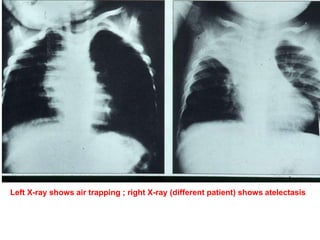

Left X-ray shows air trapping ; right X-ray (different patient) shows atelectasis

Chest X-ray forAspirated Foreign Bodies ƒ Foreign object radiopaque in 6 to 20 % ƒ CXR normal in 18 to 33 % ƒ CXR findings: –obstructive emphysema –atelectasis –pneumonia ƒ Expiratory film enhances CXR yield

Left X-ray showsair trapping ; right X-ray (different patient) shows atelectasis